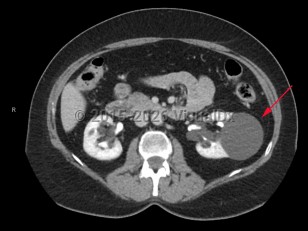

Imaging Studies image of Renal cysts - imageId=7885061. Click to open in gallery.  caption: '<span>Enhanced CT scan demonstrating left renal cyst.</span>'

Enhanced CT scan demonstrating left renal cyst.